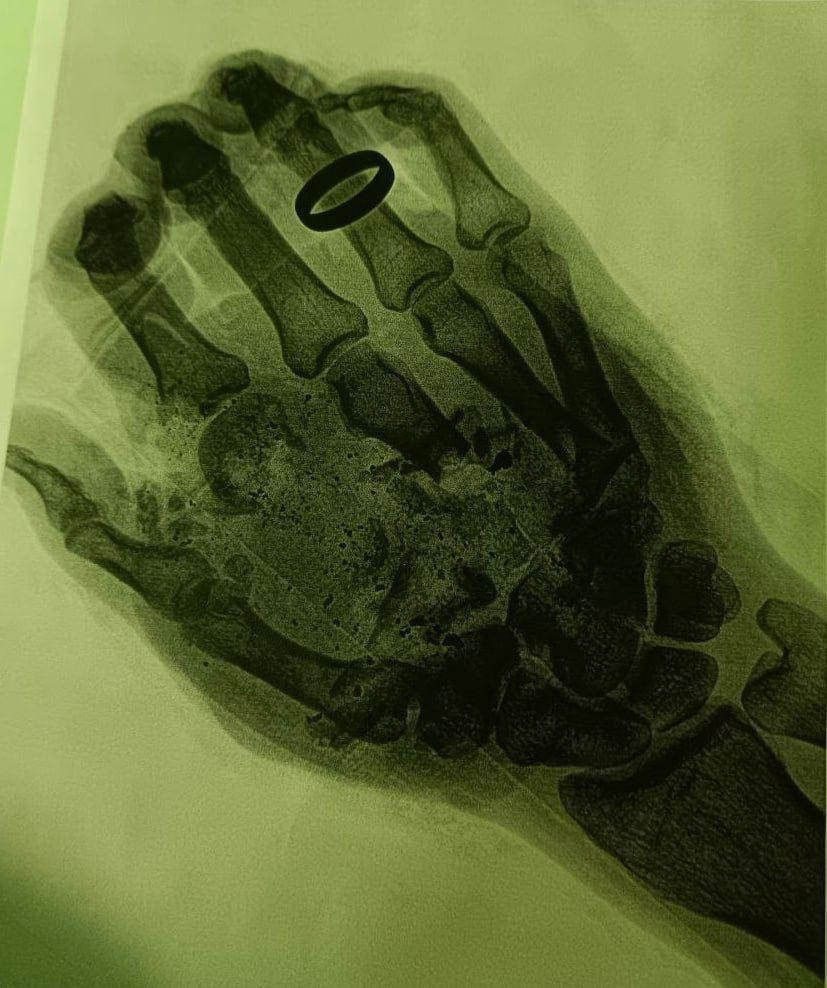

Пострадавшего 36-летнего мужчину доставили в местное медучреждение с размозжением мягких тканей кисти правой руки и фаланг пальцев. Несчастный случай произошёл во время отдыха на природе. Об этом сообщает пресс-служба Министерства здравоохранения Московской области.

«Во время первого этапа мы провели тщательную обработку ран и собрали все кожные лоскуты. Затем наложили мужчине аппарат временной фиксации. Операция прошла успешно. Чувствительность, микроциркуляцию и подвижность руки удалось сохранить», — сообщил врач-травматолог-ортопед Дмитрий Лактанов.

Сейчас мужчина чувствует себя хорошо — его выписали из медучреждения. Пациенту предстоит пройти длительный реабилитационный процесс. Специалисты в очередной раз напомнили о важности соблюдения техники безопасности при обращении с газовым оборудованием.